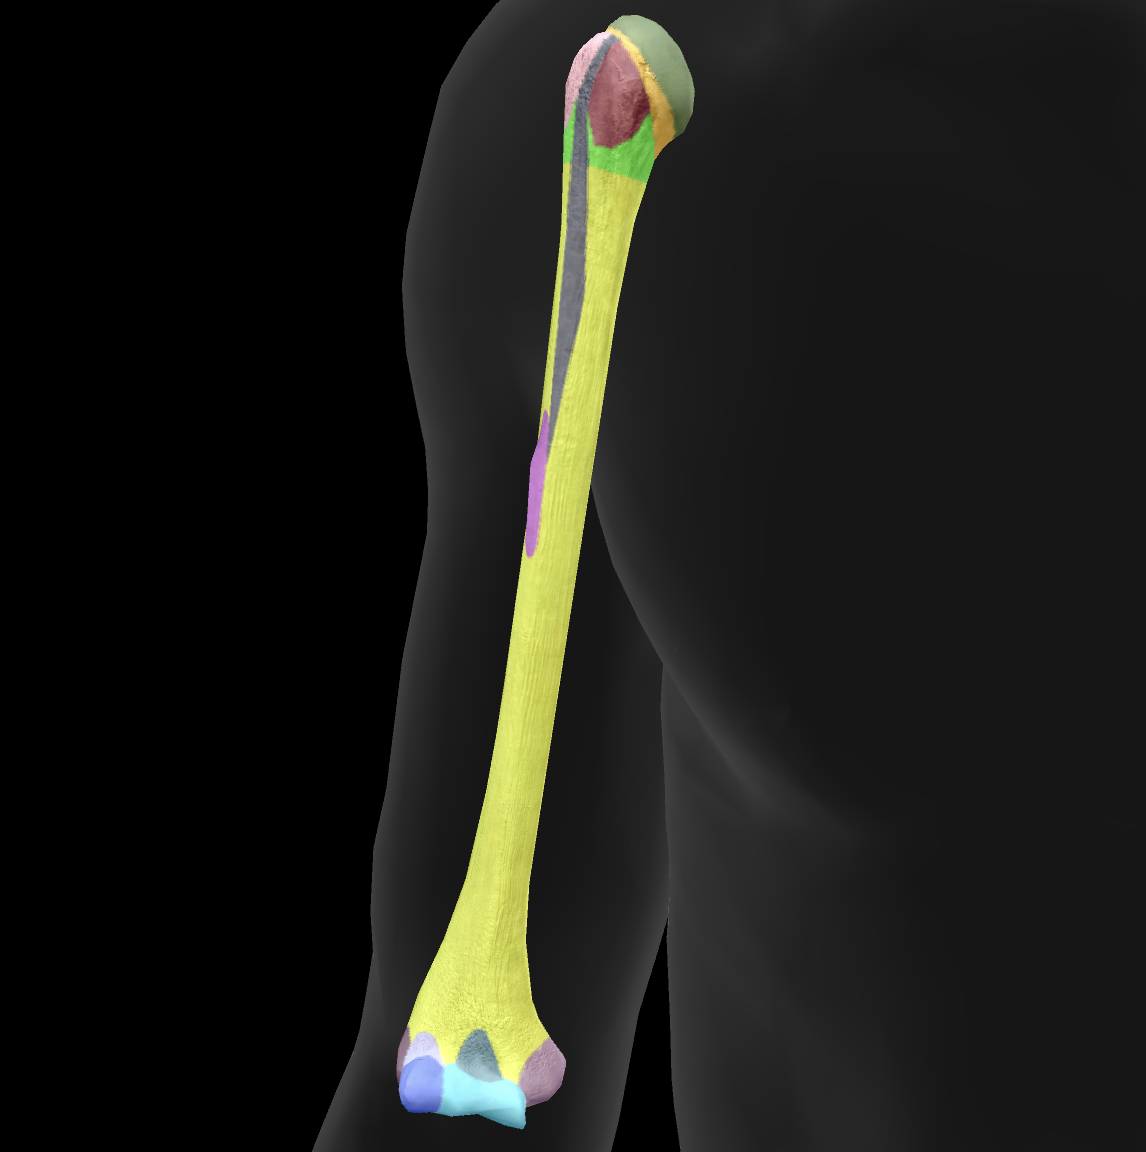

What bone is this?

ulna

What is this boney landmark?

trochlea notch

What is this boney landmark?

coronoid process

What is this boney landmark?

radial notch

What is this boney landmark?

ulnar tuberosity

What is this boney landmark?

shaft

What is this boney landmark?

head

What is this boney landmark?

styloid process

What is this boney landmark?

olecranon process

What is this bone?

radius

What is this boney landmark?

head

What is this boney landmark?

neck

What is this boney landmark?

radial tuberosity

What is this boney landmark?

shaft

What is this boney landmark?

radial styloid process

What is this boney landmark?

ulnar notch

What is this boney landmark?

lister’s tubercle